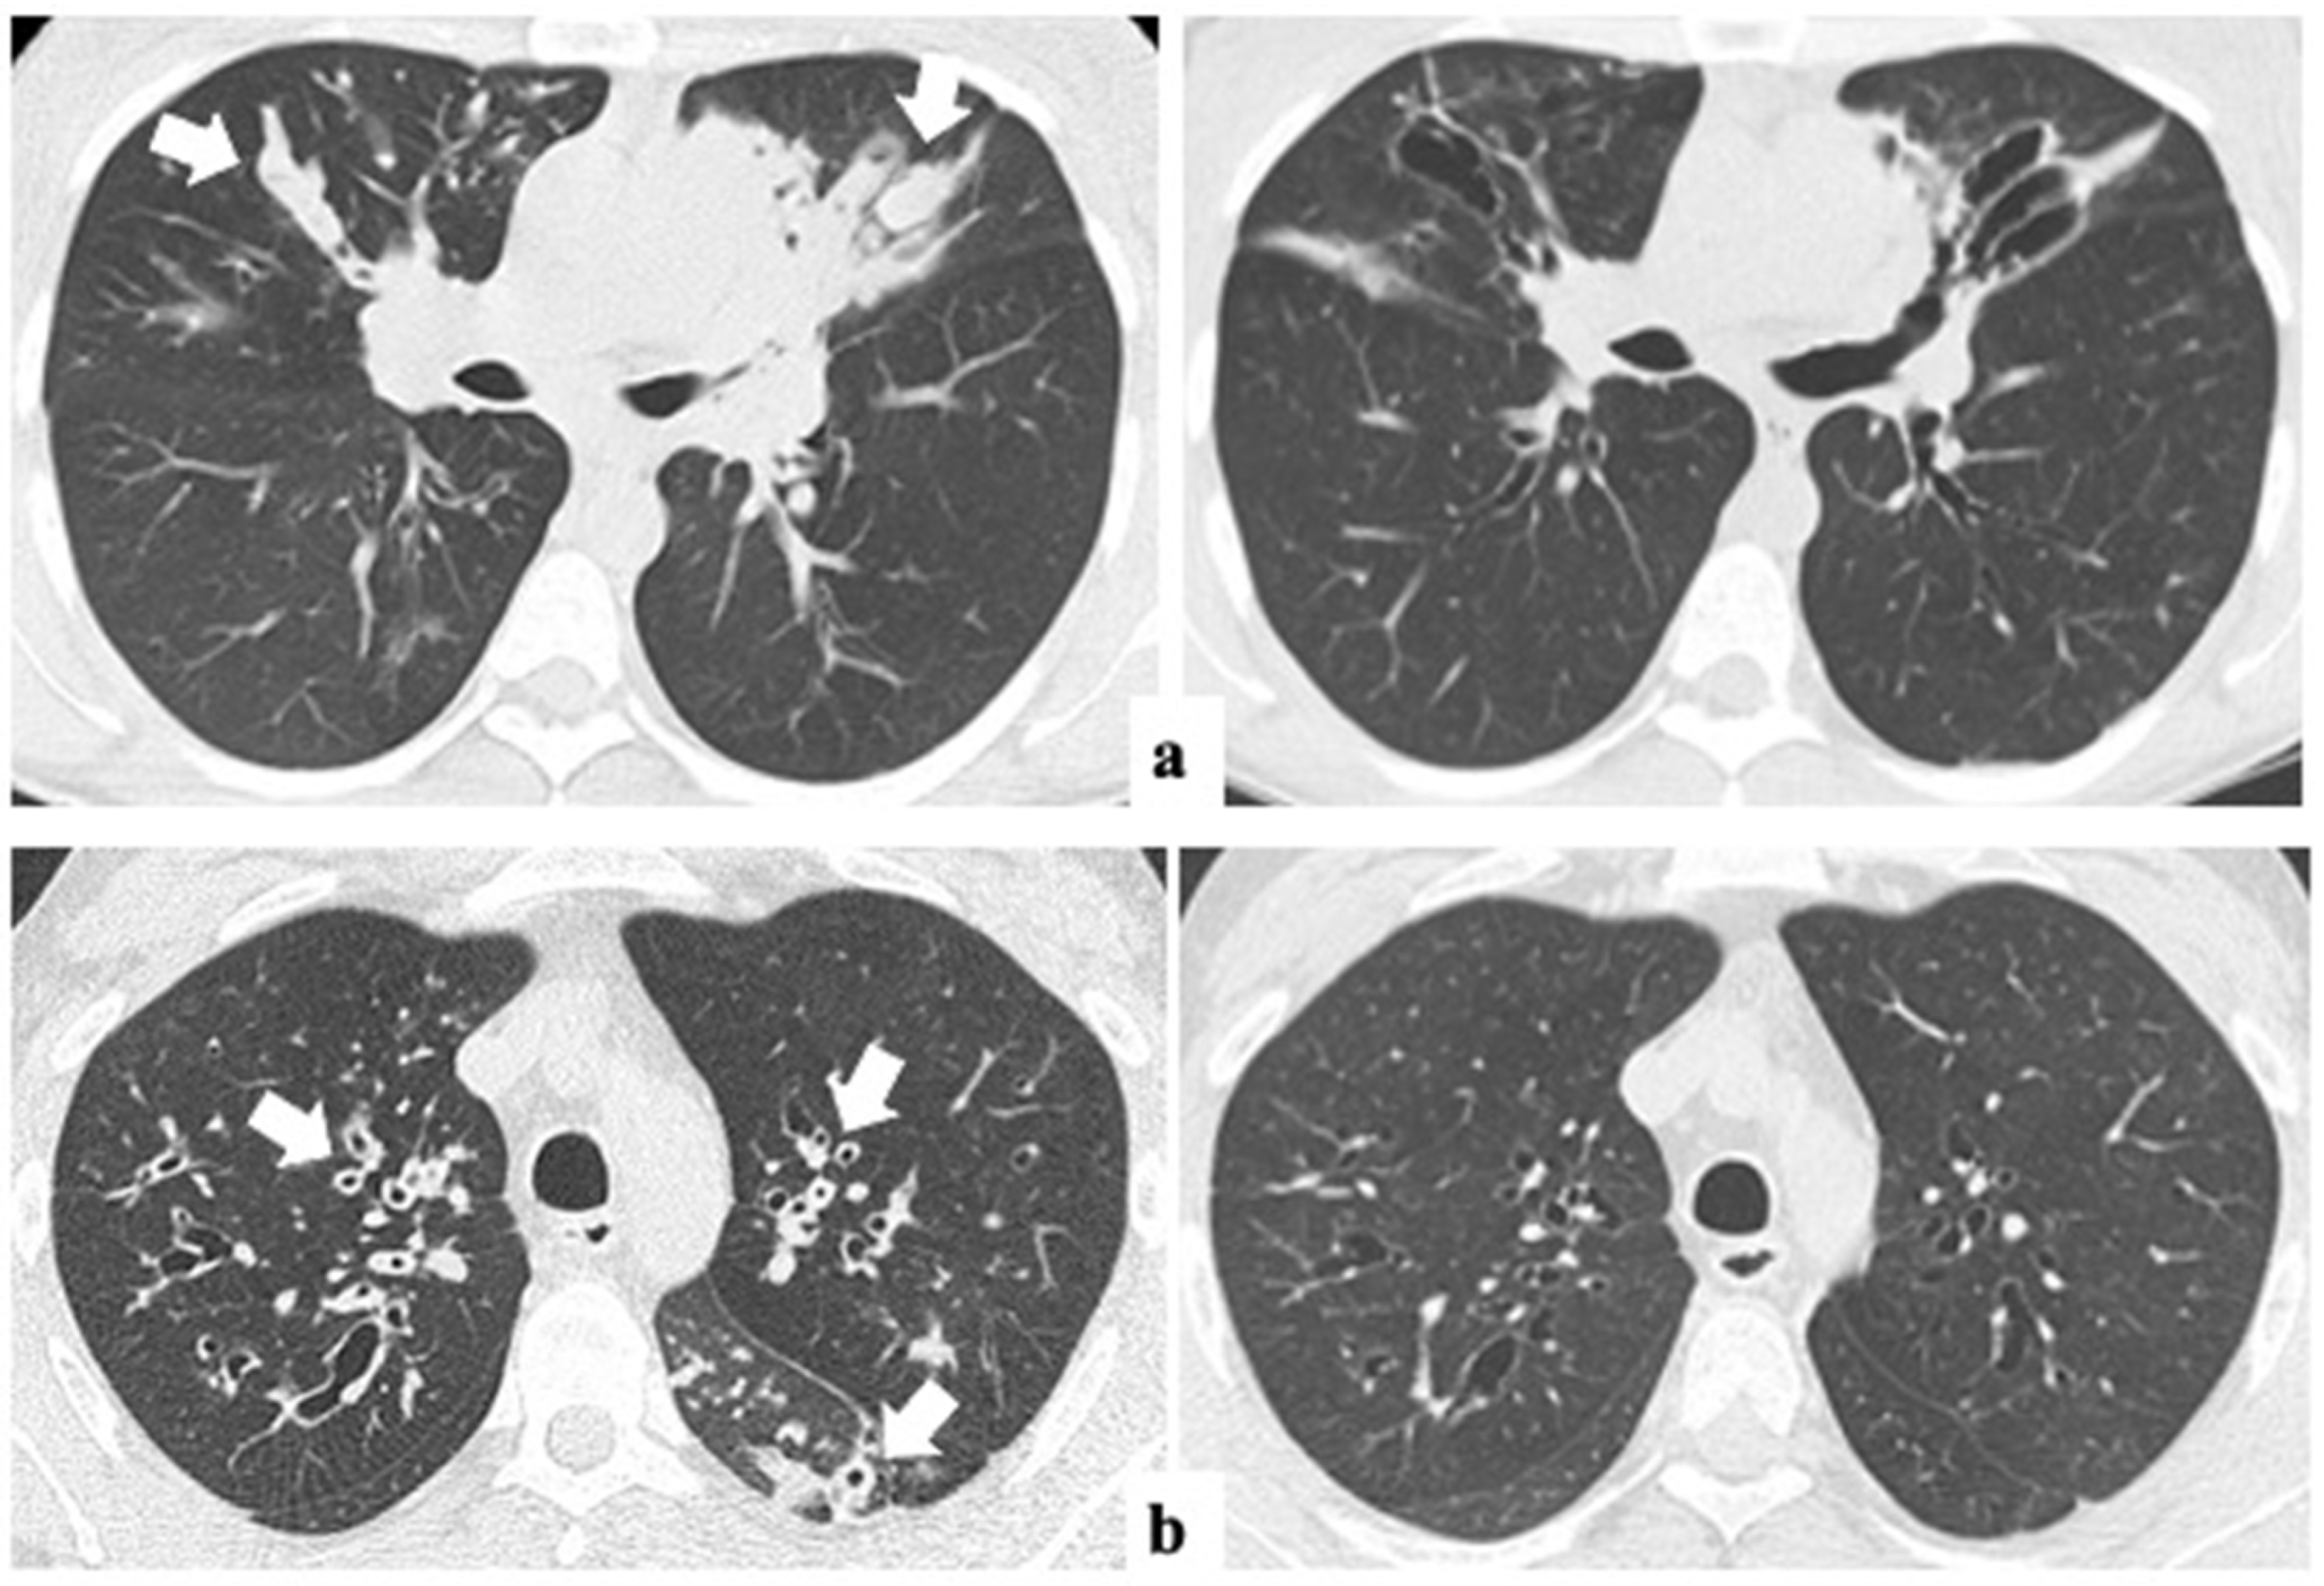

The median time interval between CT0 and CT1 was 2.5 ± 1.5 years (range from 12 to 54 months). The changes in the global Bhalla score and each specific structural subscore before and after ETI are summarized in Table 2. The global Bhalla score improved significantly (p < 0.001), from 12.2 (±2.8) to 14.0 (±2.8). Additionally, other radiological items, such as peribronchial thickening (1.4 ±0.6 vs. 1.0 ±0.4) and the extent of mucus plugs (1.6 ±0.7 vs. 0.8 ±0.6), also showed significant changes (p < 0.001) (Figure 2). None of the other parameters assessed worsened after one-year ETI.

Figure 2.

Axial lung CT images before (left) and after one-year ETI therapy (right) in two adults with CF. Dramatic improvements in mucus plugs in (a) (arrows) and peribronchial thickening in (b) (arrows) are shown. ETI: elexacaftor–tezacaftor–ivacaftor.

Similarly, BMI (22.4 ± 2.6 vs. 23.6 ± 2.6 kg/m2) and spirometry (ppFEV1 66.5 ± 19.8 vs. 77.0 ± 20.4, and ppFVC 80.6 ± 16.4 vs. 91.6 ± 14.1) showed significant improvements (p < 0.05).